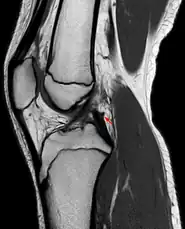

Posterior meniscofemoral ligament (Wrisberg) behind the posterior horn of the lateral meniscus close to its insertion. Sometimes wrongly interpreted as a meniscal tear.

The Posterior meniscofemoral ligament (also known as the ligament of Wrisberg) is a small fibrous band of the knee joint. It attaches to the posterior area of the lateral meniscus and crosses superiorly and medially behind the posterior cruciate ligament to attach to the medial condyle of the femur.[1]

The posterior meniscofemoral ligament is found in 64.4% of the subjects in MRI scan of the knee.[1]